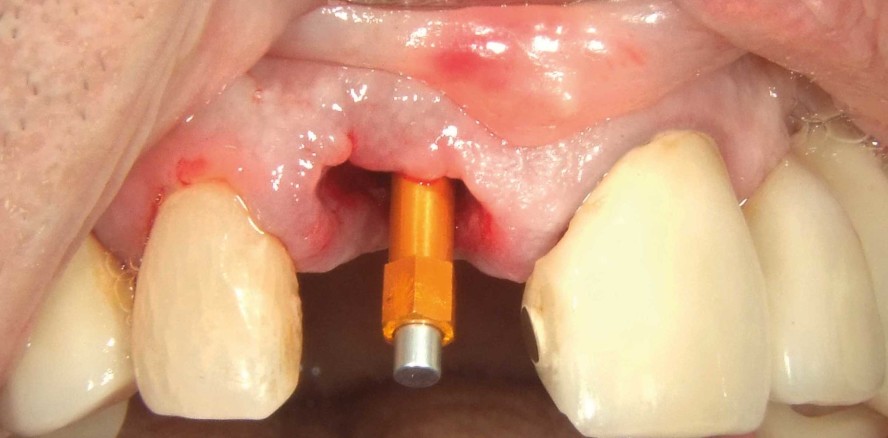

Klinisch zeigte sich ein entzündetes Weichgewebe samt frakturiertem Zahn (Abb. 1). Radiologisch konnten eine deutliche Sekundärkaries und eine apikale Läsion festgestellt werden (Abb. 2).

Der bestehende Wurzelrest wurde samt dem apikalen Granulationsgewebe vorsichtig entfernt, sodass das Maximum an Knochen erhalten werden konnte (Abb. 4). Die exakte Implantatposition wurde mittels Guided Surgery festgelegt und durchgeführt, sodass das Implantat sowohl in der vertikal als auch horizontal perfekten Position inseriert werden konnte (Abb. 5). Es wurde ein Implantat mit dem Durchmesser 4,5 und Länge 11,5 mm gesetzt (MegaGen AnyRidge). Durch das besondere Implantatdesign kann hier über die ausladenden Gewindeflanken eine sehr hohe Primärstabilität erreicht werden. Durch den gleichbleibenden Kerndurchmesser, jedoch größer werdenden Implantatdurchmesser, steht hier der maximale Knochenerhalt im Vordergrund. Der BIC (Bone–Implant Contact) wurde mittels des sogenannten Mega ISQ über einen SmartPeg bestimmt (Abb. 6). Hier konnte ein ISQ-Wert von 74 erzielt werden. Bei Werten von > 70 spricht man von einer hohen Primärstabilität und es kann eine Sofortbelastung bei Einzelzahnimplantaten durchgeführt werden. Wir füllen standardmäßig die sogenannte Jumping Distance (Raum zwischen Implantat und Restknochen) mit Knochenersatzmaterial auf, da wir so zu einem besseren Erhalt der bukkalen Kontur und einem ästhetischeren Ergebnis kommen.